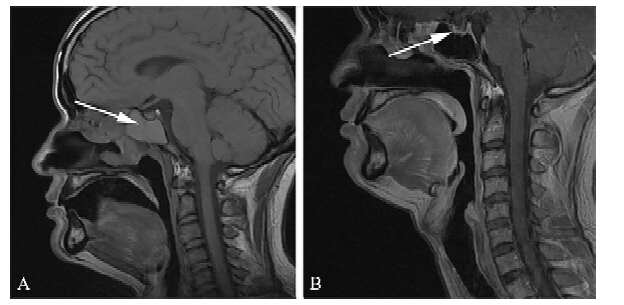

经过禁食3 d,静脉予抑酸、抑酶及抗感染等治疗后,患者上腹痛明显缓解,血清淀粉酶下降至345 U/L。但体温反复,最高39.2℃。完善上腹部MRI平扫+增强提示胰体部可见一囊实性异常信号影,大小约为26 mm×23 mm,肝S6段见一类圆形稍长T1稍长T2信号影,大小约为21 mm×14 mm。影像学诊断考虑胰体部囊实性病变为恶性肿瘤,并肝S6段转移可能(图 1)。因此我们认为是肿瘤侵袭所致的急性胰腺炎。行胰腺肿块超声引导的经皮细针抽吸(FNA)活检。 病理提示部分细胞中等大、圆形,有腺样结构趋势,部分细胞有变性,核大深染,轮廓不清,有异型性,考虑为恶性肿瘤细胞,倾向于NK/T细胞淋巴瘤,但不能完全排除胰腺原发肿瘤(图 2)。但因取材不足,无法完善免疫组织化学检测。

图 1 结外鼻型NK/T细胞淋巴瘤患者腹部MRI扫描 MRI图像在静脉期的对比度增强;A:平扫时胰体部可见一囊实性异常信号影,大小约为26 mm×23 mm,胰腺尾部一贯轻度不均匀扩张(A1);动脉期(A2)病灶边界信号增强,延迟动脉期(A3)时信号进一步增强;B:在2个疗程的化学治疗后,胰腺病灶缩小至13.2 mm×11.7 mm |

患者最终被诊断为结外鼻型NK/T细胞淋巴瘤,侵袭胰腺与肝脏。患者接受了8个疗程的静脉化学治疗及2次鼻咽部的放射治疗(约60 Gy/30f)。化学治疗包括EPOCH方案(依托泊苷、阿霉素、环磷酰胺、长春新碱、泼尼松)2个疗程,然后EPOCH+培门冬酶2个疗程,然后EPOCH+左旋门冬酰胺酶及EPOCH+左旋门冬酰胺酶+博来霉素各1个疗程,最后为CHOP+博来霉素2个疗程。此外,行腰椎穿刺及鞘内注射甲氨蝶呤预防中枢神经系统淋巴瘤。患者胰酶水平在第1程化学治疗后恢复正常。第2程、第4程化学治疗后疗效评估为部分缓解。 第6程化学治疗后胰腺病灶消失,肝脏中的病灶几乎消失。鼻咽部肿物在第2程化学治疗后缩小至11.5 mm×3 mm(图 3),在第8程化学治疗后几乎消失。化学治疗结束9个月后患者因发热3 d来我院就诊,复查鼻咽部CT平扫+增强提示左颌下淋巴结稍大,鼻咽部及鼻腔、副鼻腔未见明确肿块影。复查上腹部CT平扫+增强提示胰腺体部瘤灶基本消失,肝、脾稍大。予头孢呋辛抗感染治疗近10 d仍有午后反复低热,同时完善相关检查未发现明确感染灶,考虑为肿瘤复发,予甲氨蝶呤10 mg每周1次及泼尼松10 mg每日2次,口服后体温下降,患者拒绝再次化学治疗,于诊断20个月后死于肿瘤复发及呼吸道感染。

由于肝脏亦受侵袭,我们排除了原发于胰腺的淋巴瘤。鼻咽部肿物的病理结果证实了结外鼻型NK/T细胞淋巴瘤的诊断,所以我们认为胰腺和肝脏病变是结外鼻型NK/T细胞淋巴瘤继发的。治疗完成后,胰腺及肝脏病变的缩小甚至消失,更进一步证实了我们的诊断。